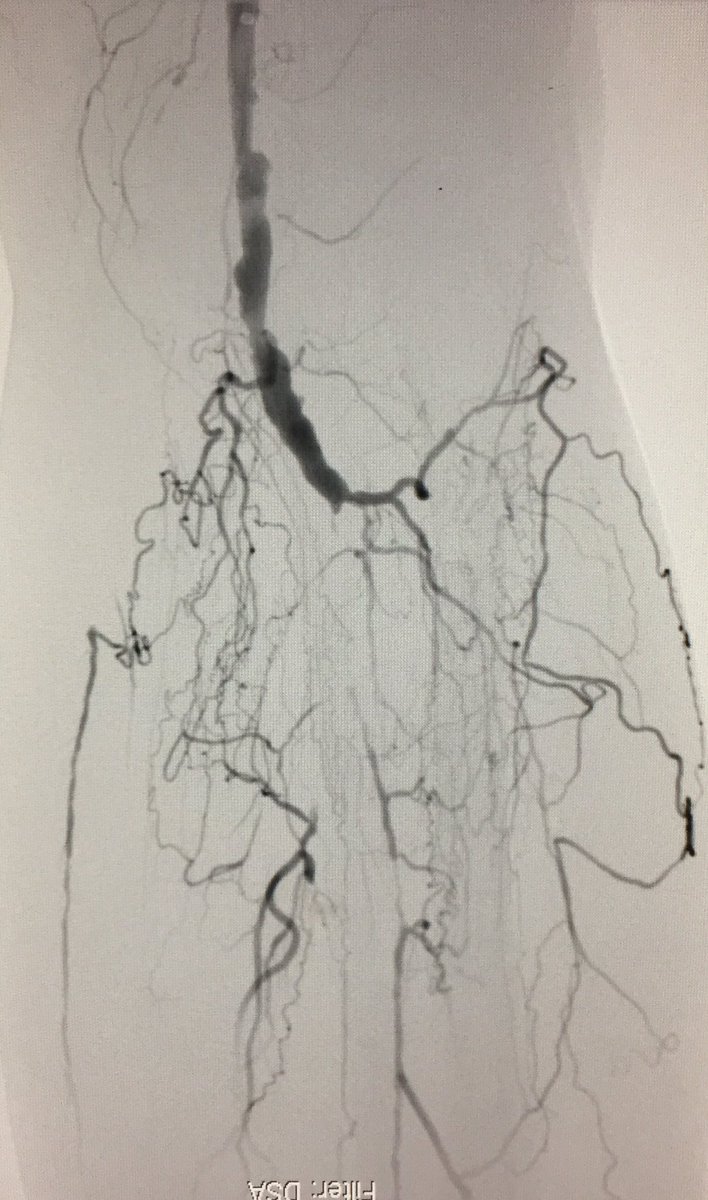

An image is worth a 1,000 words - what does this one depict ? Participate in quiz here🔗pcronline.com/Cases-resource…

🖼️submitted by Eirini Dri, Sofia Vaina, Anastasios Milkas, Konstantinos Tsioufis from 🇬🇷 and selected for #EuroPCR

#interventionalcardiology #cardiotwitter